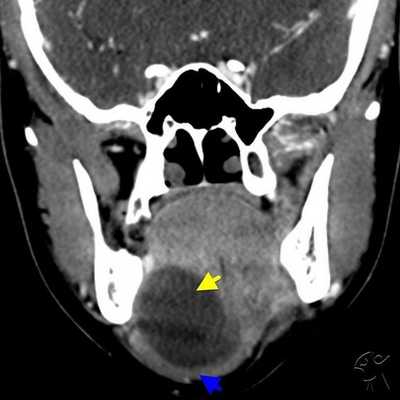

КТ-признаки слюннокаменной болезни

Отечность, увеличение околоушной и поднижнечелюстной областей, не проходящие после приема фармацевтических препаратов - показание к лучевой диагностике. Симптомы обуславливает не только сиалоаденит. Слюннокаменная закупорка (сиалолитиаз) определяется после КТ-сиалографии по следующим признакам:

- Увеличение размеров поврежденного органа;

- Сохранение однородности структуры;

- Расширение протока.

Дополнительно врач лучевой диагностики укажет плотность ткани. Признак является дифференциальным маркером определения эффективности проводимой терапии с целью отслеживания динамики на повторных томограммах.

Тонкосрезовая СКТ головы и слюнных желез с трехмерным моделированием (3D) создает пространственную структуру, с помощью которой врачи устанавливают внутрипротоковое расположение камня.